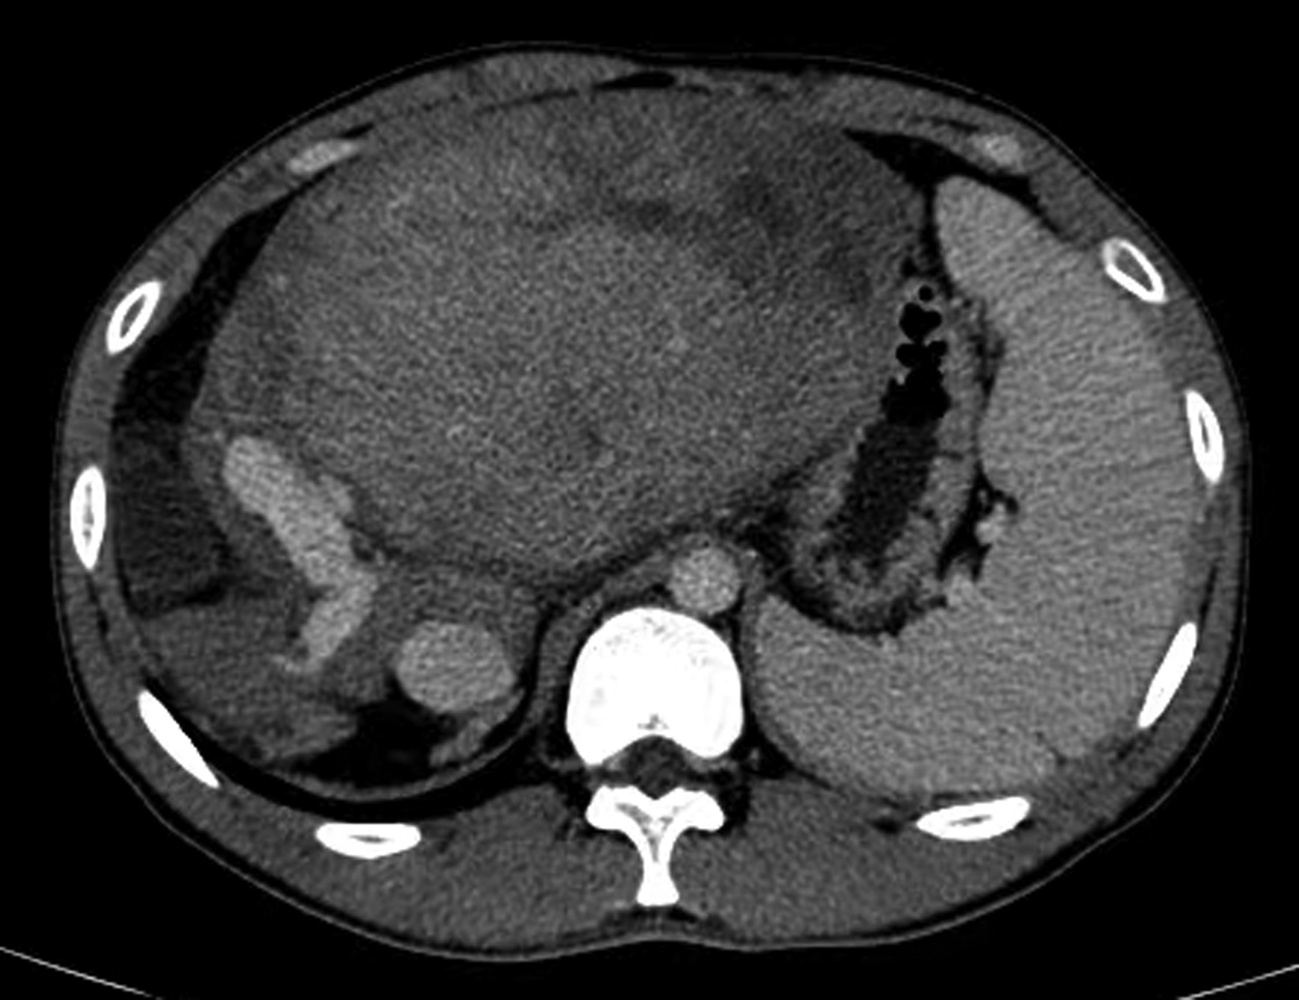

Chronic pancreatitis caused by incomplete pancreas division: A case report

Meili DONG, Ruihua ZHANG, Tengfei LI, Yang WANG, Xiaoyu WEN

2022, 38(11): 2578-2580. DOI: 10.3969/j.issn.1001-5256.2022.11.028

Abstract(859) HTML (576) PDF (2085KB)(55)

Abstract: